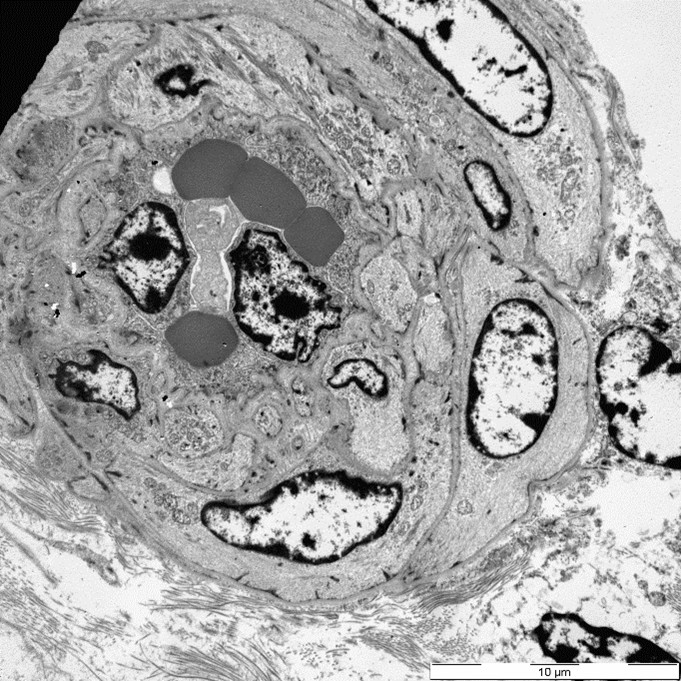

Three glomeruli were available for ultrastructural evaluation by transmission electron microscopy (TEM). One glomerulus had collapsed capillary loops and fibrillary material in Bowman’s space. All glomeruli had numerous large electron dense deposits within the capillary walls in intramembranous, subendothelial, mesangial, and subepithelial locations. Subepithelial deposits were associated with spike-like projections and circulations of glomerular basement membrane material. One glomerulus is segmentally sclerotic with loss of podocytes and denuded capillary walls. The afferent/ efferent arterioles have severely hypertrophied endothelial cells with markedly narrow lumens. In one of the arterioles the circulating erythrocytes are distorted.

Closing out our fourth conference, this case graced participants with an opportunity to see a lovely correlation between light microscopy and electron microscopy (EM) findings. It’s not often that EM images are sent in as part of Wednesday Slide Conference submissions, but it’s always a treat when they are! Many thanks to the contributor for providing both a wonderful slide and beautiful EM images. Together, they truly did paint the whole picture for this EM-worthy condition.Because the EM images were provided, a review of the ultrastructural anatomy of a glomerular capillary profile and its surrounding structures ensued, with focus on the primary and secondary foot processes of the visible podocyte and the different layers of the glomerulus. However, the main show was the electron-dense, granular, irregularly shaped clumps of immune complexes (IC) within subepithelial, intramembranous, and subendothelial spaces of the glomerular tuft. Having IC deposition demonstrably in all three of those locations within the glomerulus assisted with the determination of the “mixed” type of glomerulonephritis in this case. Conference participants favored “membranoproliferative” based on the H&E slide, but acknowledged that this case did not fit 100% into that box upon review of the EM images and accepted the use of the term “mixed” in discussion. Typing of glomerulonephritis is more difficult to do with light microscopy alone due to some histologic similarities between the types, bringing home the point that, for definitive characterization of glomerulonephritis, EM is indispensable.